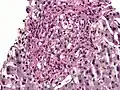

- Histoplasma. PAS diastase stain.